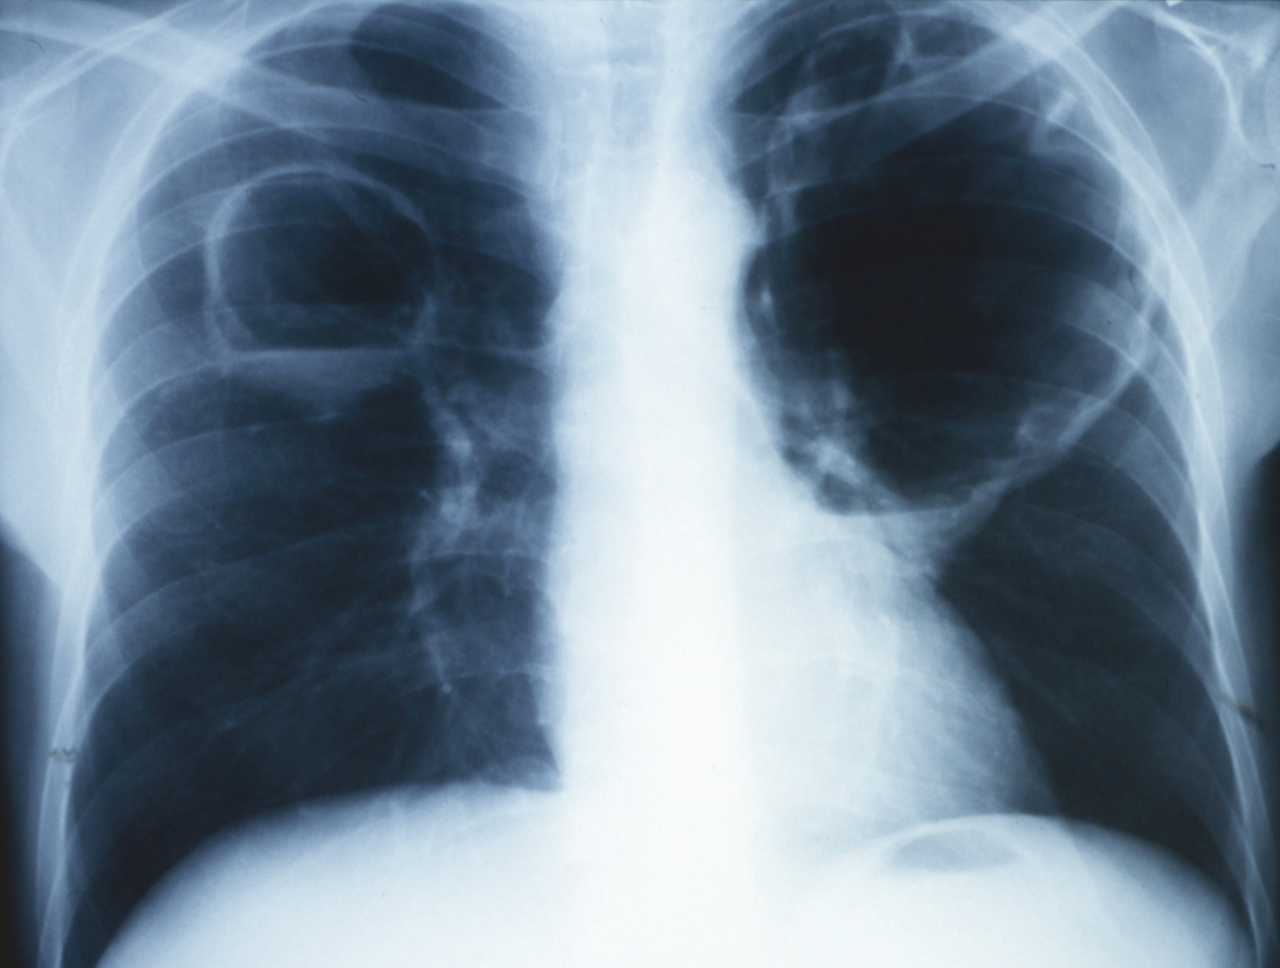

Quel est votre diagnostic ?

Il s'agit d'abcès du poumon. Les abcès du poumon, uniques, ou multiples comme ici, produisent des opacités excavées à parois épaisses, localisées dans 70 % des cas dans les zones postérieures. Les agents infectieux en cause sont le plus souvent les bacilles à Gram négatif et les streptocoques d'origine bucco-dentaire chez l'adulte, et le staphylocoque chez l'enfant. Le germe en cause ici est le staphylocoque. Les pneumopathies à Staphylococcus aureus sont rares et correspondent à moins de 5 % des pneumopathies communautaires. Elles surviennent souvent dans un contexte post-grippal en raison de l'atteinte de l'épithélium respiratoire qui favorise l'infection par S. aureus.